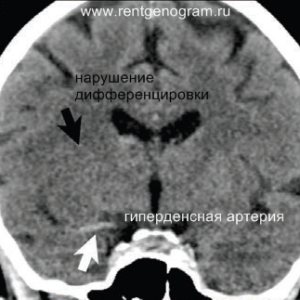

Ранние признаки ишемического инфаркта на КТ:

- уменьшение дифференциации серого и белого вещества;

- фокальная гипоплотность (включая островки, подкорковые ядра и кору);

- утолщение коры и сужение борозд;

- сглаживание контуров извилин и борозд;

- повышенная плотность в артерии (может быть выявлен гиперденсный тромб, обычно в СМА или ВСА);

- незначительная асимметрия мозговых структур в базальных ядрах;

- через 4-5 часов могут появиться признаки уменьшения плотности поврежденных структур мозга.